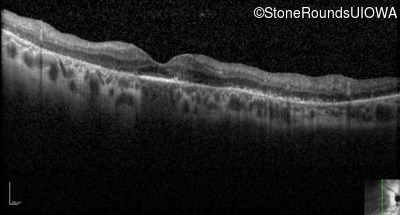

Optical Coherence Tomography - Left - 20/70 +1

Exemplar / OCT Stack